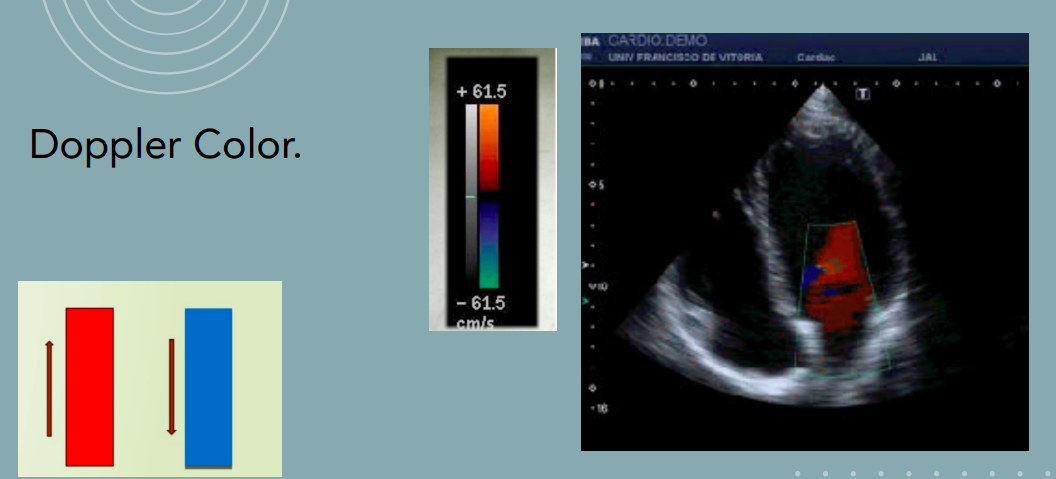

- Doppler color: permite visualizar flujos sanguíneos.

Doppler color: muestra regurgitaciones.

Doppler color: regurgitaciones mitral o tricúspide.

Doppler espectral: velocidad de flujos transmitral y transtricuspídeo.